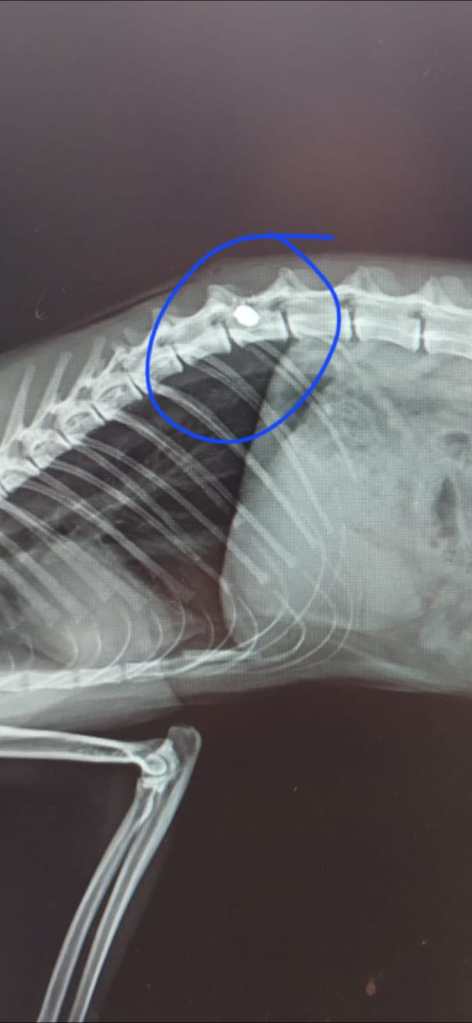

Tra le vittime di questa pratica (che, se confermata, sarebbe illegale, oltreché crudele), una gatta di proprietà di nome Spadina è stata gravemente ferita da un colpo alla colonna vertebrale, riportando danni irreversibili che ne hanno compromesso l’uso degli arti posteriori. Le condizioni cliniche dell’animale indicano una paralisi permanente. La zona ospita, oltre ad animali domestici, una colonia felina regolarmente accudita da cittadini responsabili, e a breve vi saranno affissi i cartelli che ne certificheranno ufficialmente la presenza e la tutela secondo la normativa vigente.